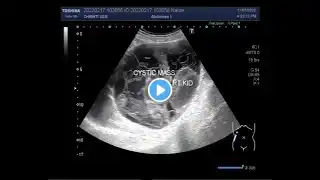

Multi Locular Cystic Nephroma

MULTILOCULAR CYSTIC NEPHROMA WITH SHRUNKEN KIDNEY.